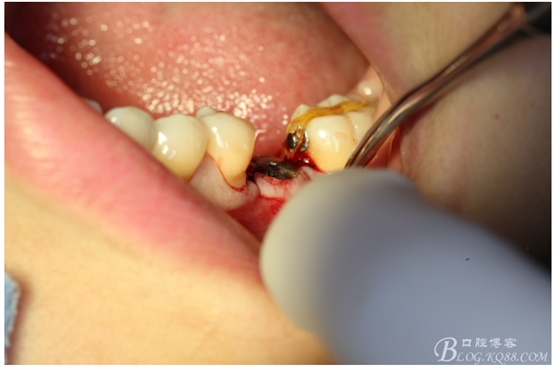

處理:必蘭麻局部麻醉切開37遠中牙齦,植入mini支抗釘一枚,37近中鄰面粘舌側扣,皮鏈輕力牽引,3周更換。

三月后37扶正